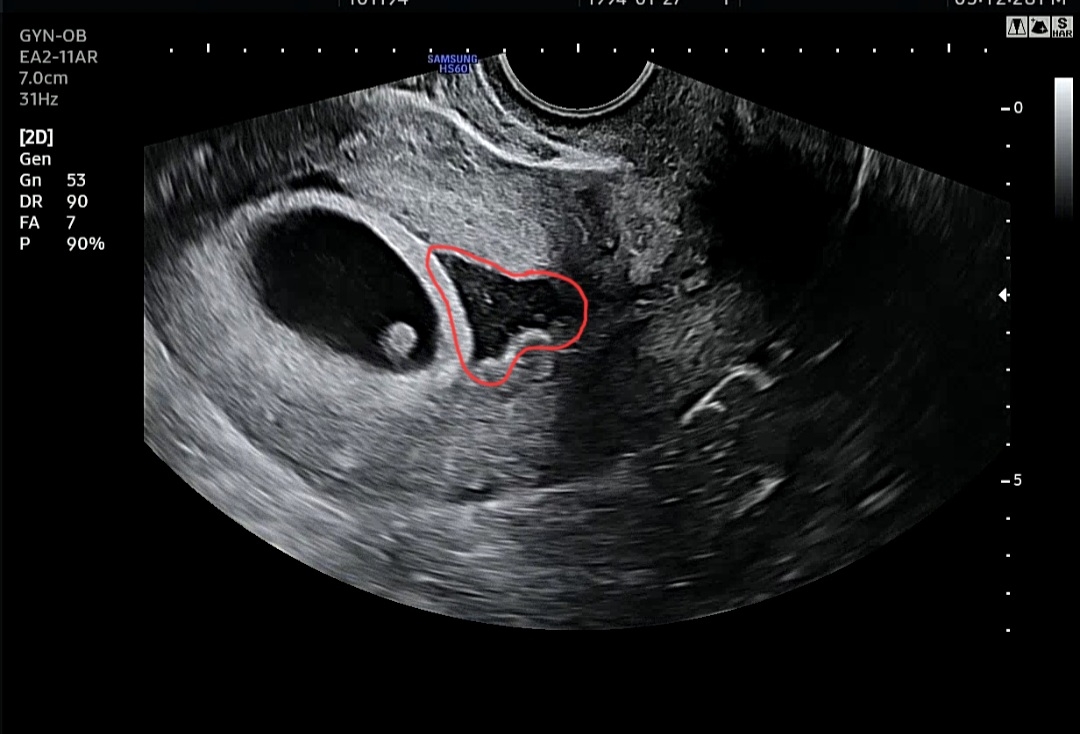

6주5일차 피고임

2주전에 아기집만 보고 왔다가 오늘 다시 병원에 내원해서 심소도 듣고 왔어요! 근데 원장님이 빨간표시 저만큼 피고임이 있다 하시더라구요ㅠ 원장님은 괜찮다고 약 처방 이런거 안해주셨는데 바로 어제 넘 심한 스트레스를 받았어가지구... 괜히 불안하네요ㅠ.ㅠ 원장님이 괜찮다하니까 괜찮은거겠지요...?ㅠ